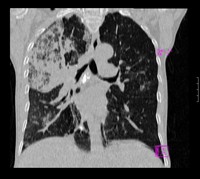

女67岁,咳嗽咯白痰伴纳差一月。右肺呼吸音低可闻及湿罗音。白细胞及淋巴细胞不高,无发烧

1、右上胸廓塌陷,纵隔气管右移

2、病灶靠后方,一般结核多见一点

3、病灶内,纵隔内有少许钙化灶

3楼的肺细支气管肺泡癌也不能完全排除,毕竟患者年纪大,病史短,临床上感染症状不明显,建议短期内复查吧